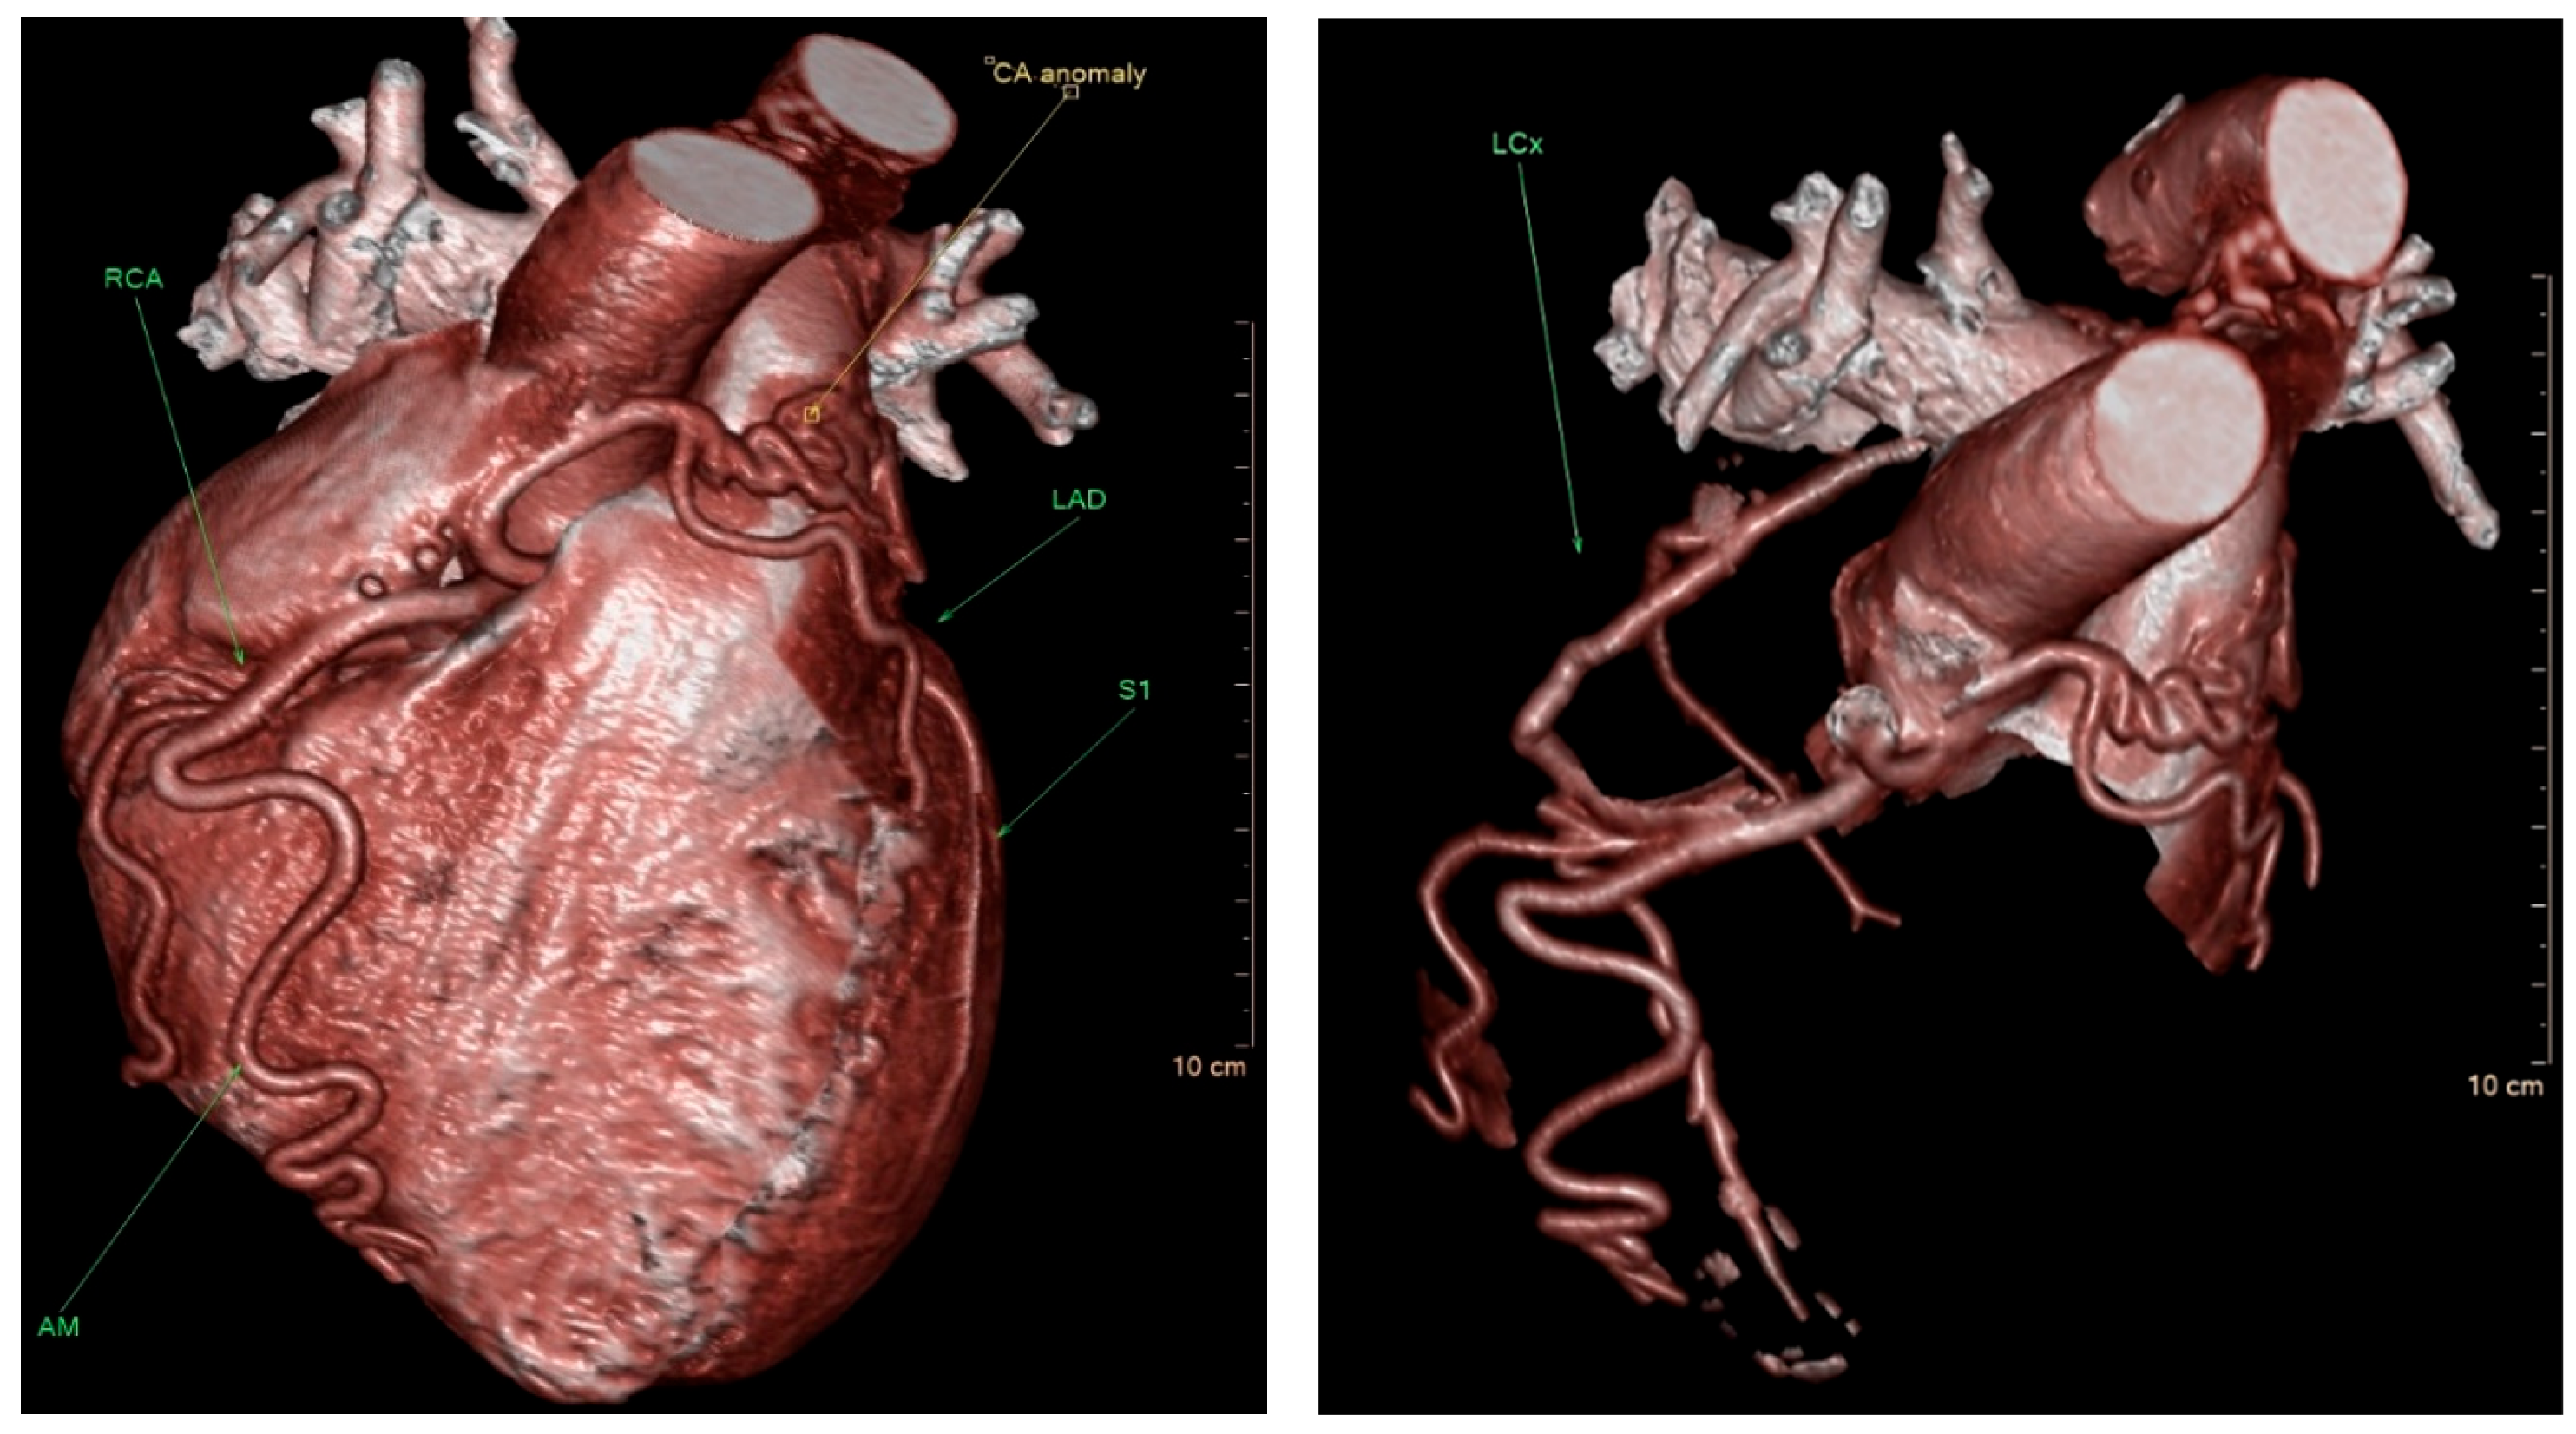

Figure 1). Given the patient’s persistent symptoms and the angiographic findings, further evaluation was pursued. Multidetector computed tomography (MDCT) of the heart was performed, which confirmed the diagnosis of ALCAPA. The MDCT demonstrated coronary arteries originating from the RCC, including the left anterior descending coronary artery (LAD) with a coronary–pulmonary artery (PA) fistula, and an anomalous origin of the left circumflex (LCx) coronary artery from the right pulmonary artery (RPA) (

Figure 2).

In this case, the patient presented with symptoms of heart failure and angina, which led to the diagnosis of ALCAPA. The MDCT of the heart revealed an anomalous and separate origin of the LCA from the RCC, as well as an anomalous origin of the LCx from the RPA. This diagnosis was confirmed by surgical excision of the anomalous LCx and reimplantation into the ascending aorta [